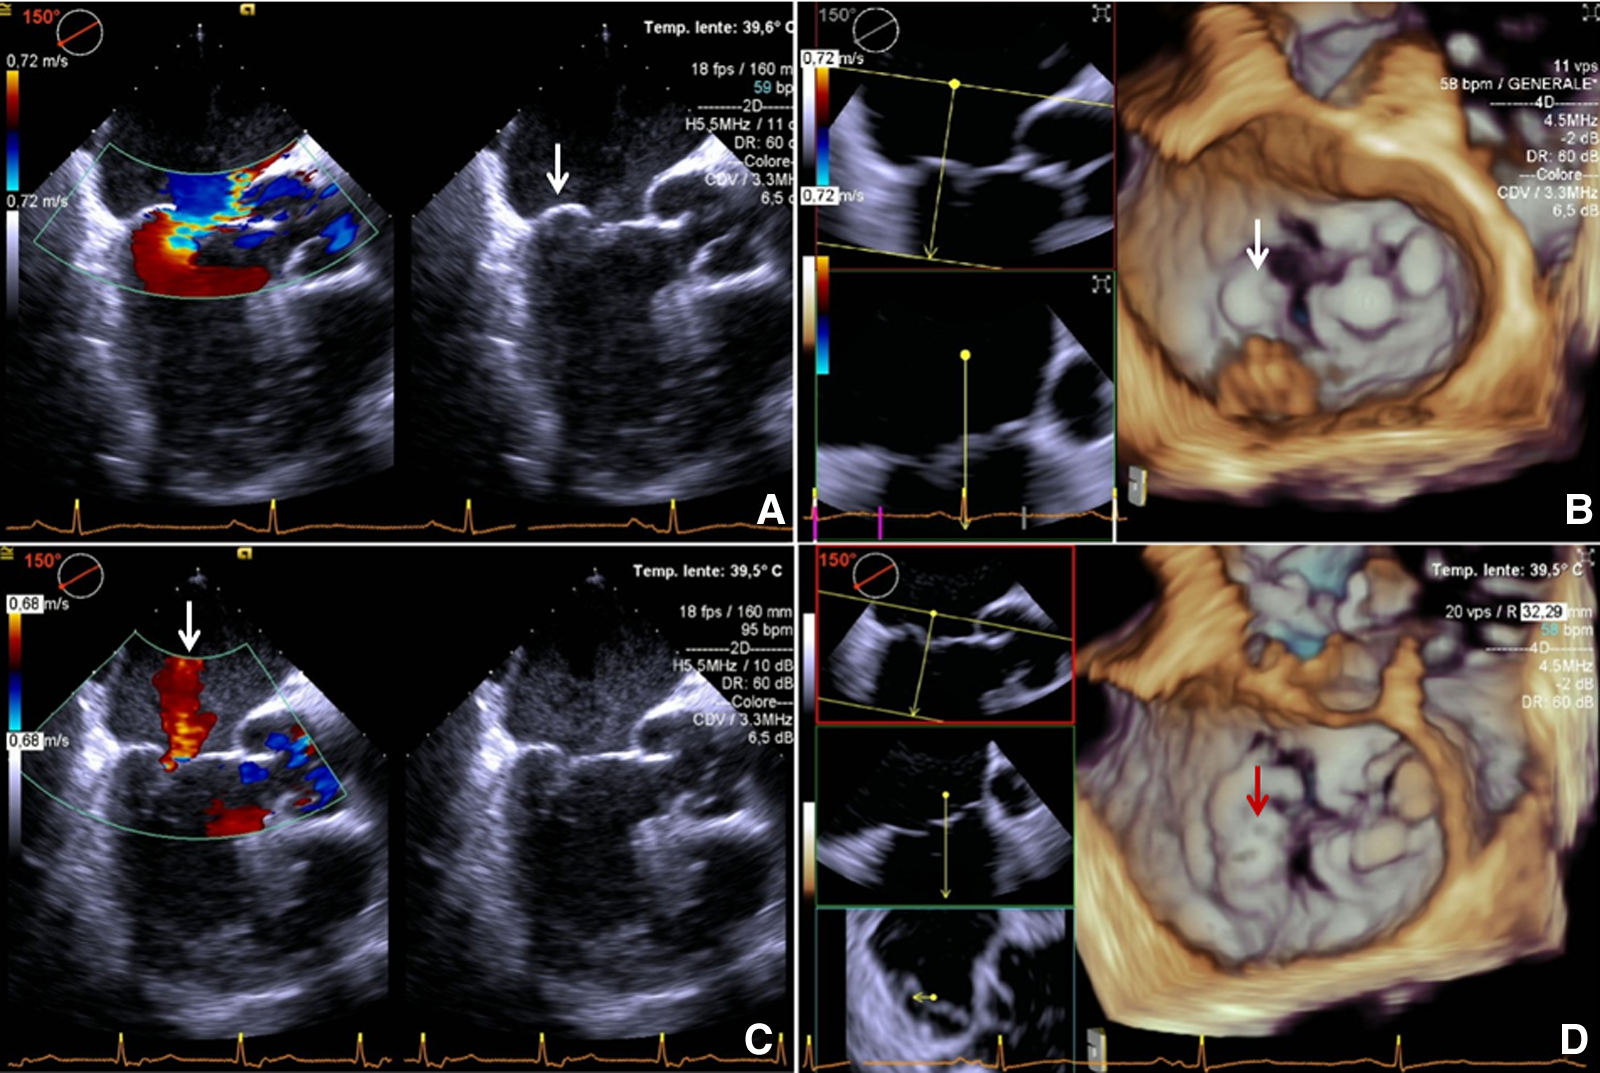

On POD 3, physical examination revealed 3/6 systolic heart murmur and postoperative transthoracic echocardiography (TTE) showed severe MR recurrence. TEE confirmed these findings, in the absence of native/artificial chordal rupture and in the presence of significant LVRR, causing NCRE and reprolapse of the treated leaflet (Figures 1A,B). Preoperative end-diastolic volume index (iLVEDV) was 98 ml/m2, and postoperative iLVEDV was 81 ml/m2.

Intraoperative transesophageal echocardiography. (A,B): before retensioning procedure 2D + color Doppler and 3D; eccentric regurgitation jet directed to AML and reprolapsing PML (arrow). (C,D): after retensioning procedure 2D + color Doppler and 3D: (C) central postprocedural mild MR (arrow) is showed. (D) Mild residual PML prolapse is highlighted (arrow) and a good coaptation between AML and PML is reached. AML, anterior mitral leaflet; MR, mitral regurgitation; PML, posterior mitral leaflet.

Technique

In the reported case, residual MR was trivial after the first procedure. On postoperative day 3, recurrence of severe MR was reported (Figures 2A,B). Therefore, we decided to undergo a new surgery.